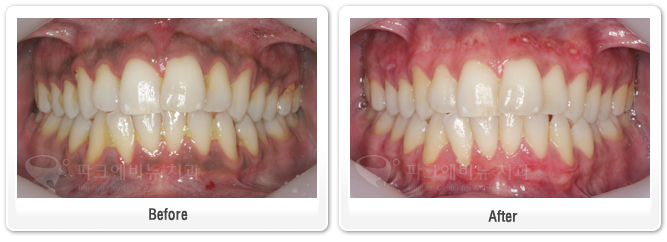

< 잇몸미백, 잇몸박피 >